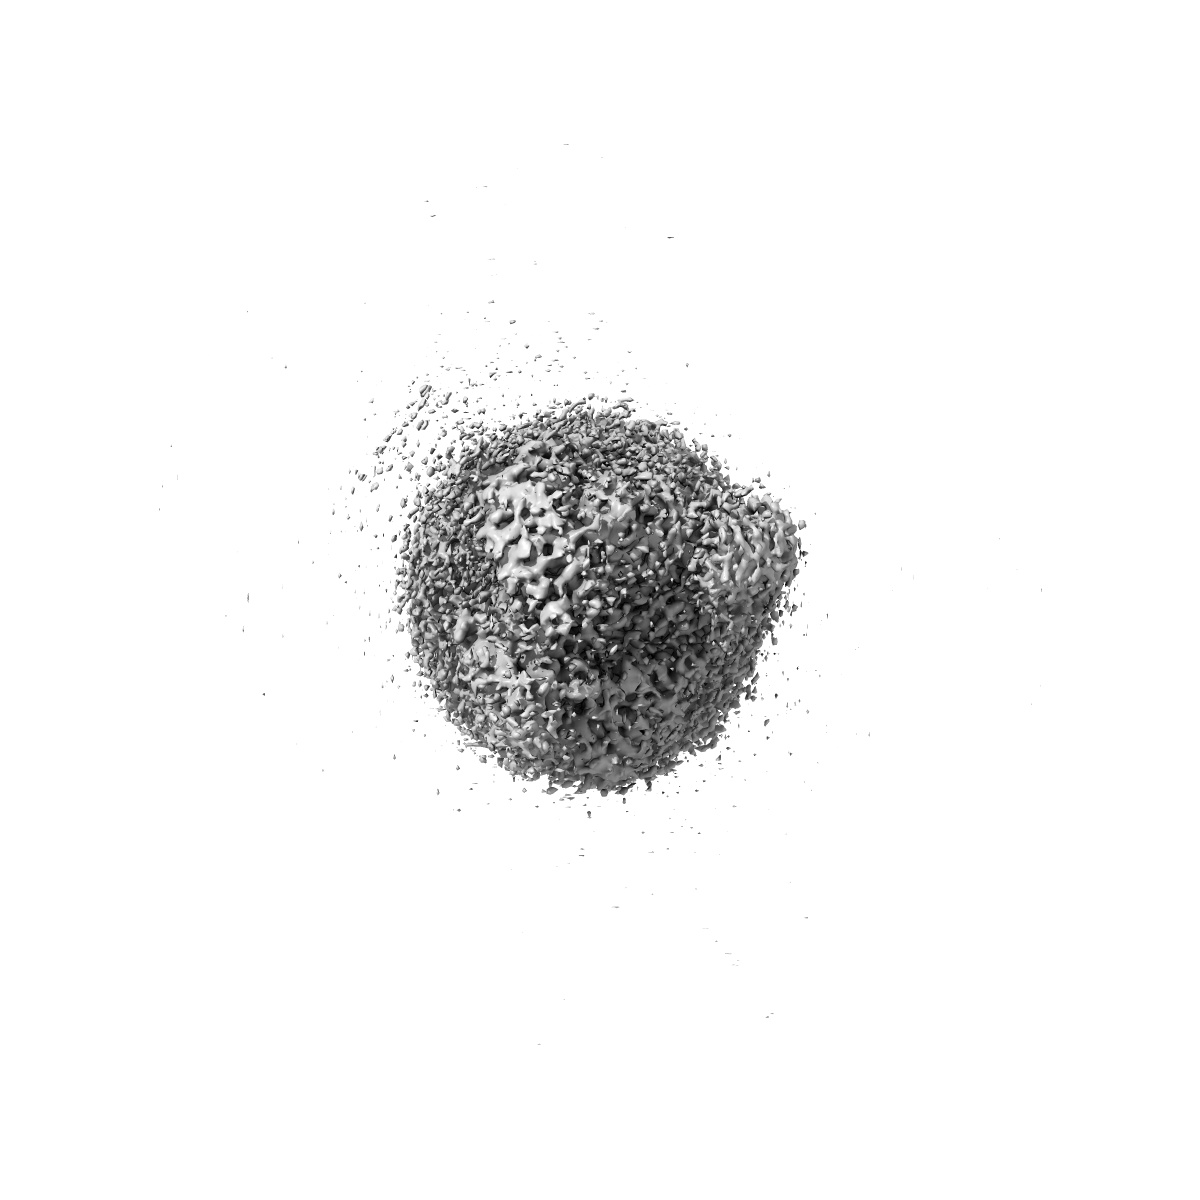

Cryo-EM structure of the non-acylated tirzepatide (LY3298176)-bound human GLP-1R-Gs complex

Single-particle3.0 Å

Sample: Cryo-EM structure of the human glucagon-like peptide-1 receptor in complex with non-acylated_tirzepatide and G protein